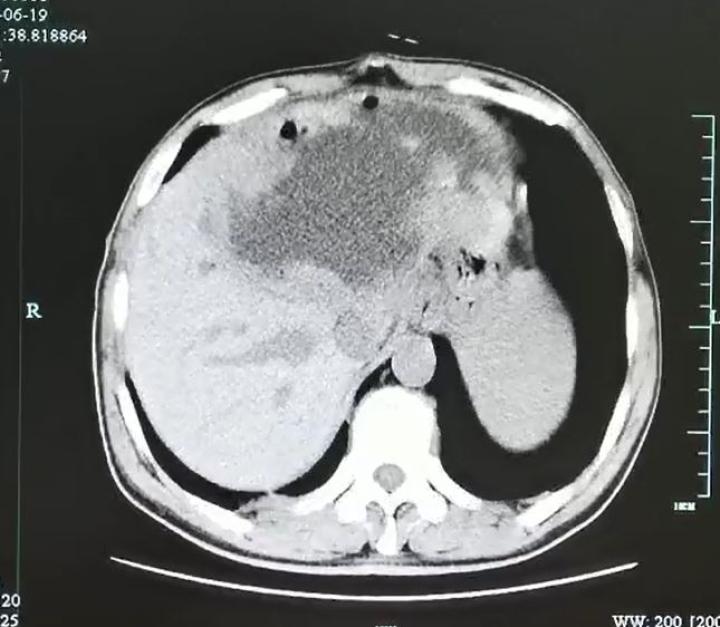

入院后腹部CT检查发现肝脓肿壁上长了很多肿瘤样的结构,而且壁很厚。看来这个肝脓肿不简单。

为了让脓球变小,进一步追查“元凶”,医生在超声指引下给谢师傅做了脓球的穿刺引流。结果大量的灰白色脓液被顺利引出,但是经过一系列的检查后,却没有发现细菌、真菌、结核和恶性肿瘤的“踪迹”。那谢师傅到底得了什么病呢?

经过肝胆外科、感染科、影像科等多学科会诊及讨论后,贾长库主任、沈伟敏主任医师、徐孙兵副主任医师等,果断地为患者进行了手术将左半肝切除,完整地拿掉了这个迷雾重重的病灶。

谁都没有想到,病理显示脓肿壁上大量的肿瘤样结构竟然是肉芽肿性炎性肿块,里面甚至还爬满了灯泡状、壳厚的华支睾吸虫虫卵,脓肿内多得数不清,看得人头皮发麻。